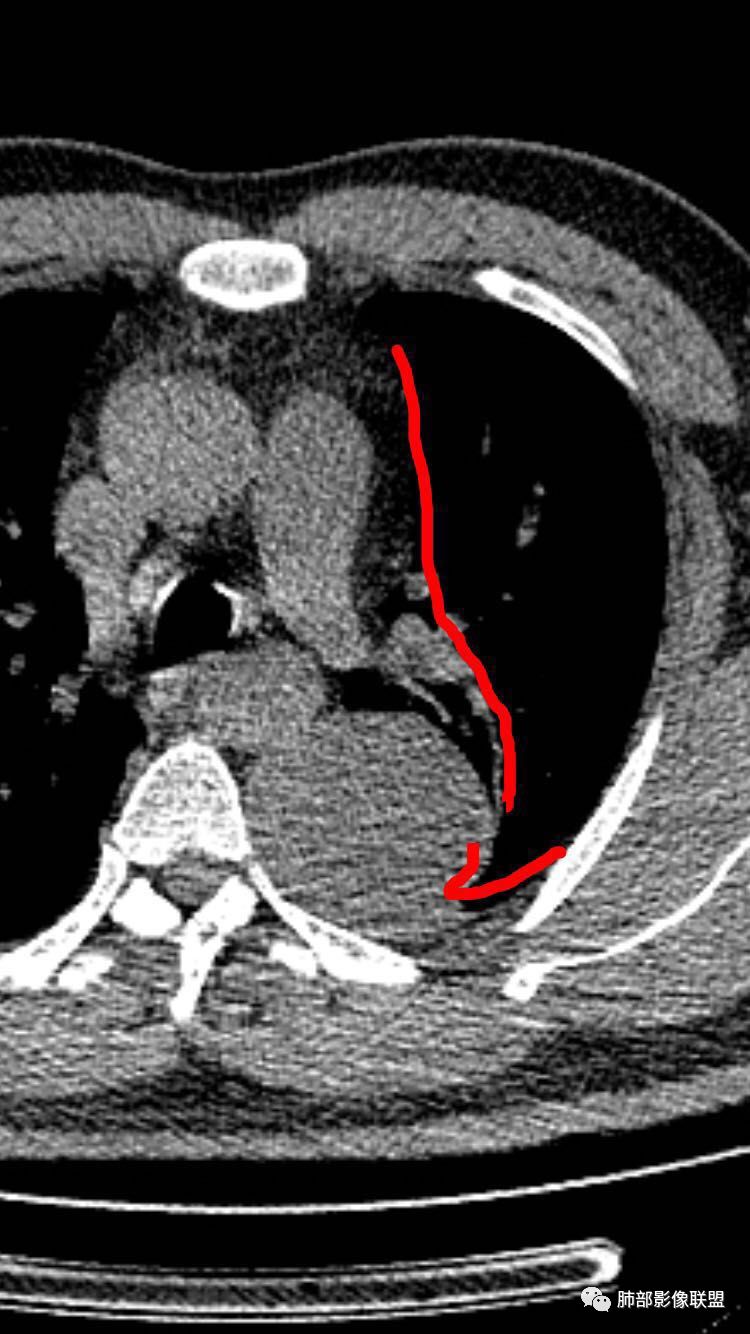

崔刚:左侧胸膜外病变,胸膜掀起,考虑神经鞘瘤。

红日东升:左侧胸椎旁肿块,边缘清晰光整,冠状位见D字征,未见支气管进入,肺组织受压表现,定位肺外。轻度强化,密度稍不均匀,临近肋骨变细,未见肺动脉供血,考虑良性肿瘤,神经源性可能。右肺下叶病灶,轻度强化,血管显影,边缘平直、凹陷,考虑炎性病变。

左肺下叶脊柱旁病灶,可见胸膜尾征,均匀强化,临近椎间孔未见扩大,考虑孤立纤维瘤,鉴别诊断神经源性肿瘤,右肺下叶病灶边缘平直,明显均匀强化,边缘清楚,考虑机化性肺炎。

张帅:患者中年男性,咳嗽 咳痰3月,痰为白色粘痰,左上肺病灶,边缘光滑,周围未见毛刺 分叶,肺组织受挤压,与胸膜关系密切,部分层面与胸膜脂肪间隙消失,有胸膜尾征,病灶定位于胸膜,病灶增强可见强化,边缘可见增强血管,内可见低密度区,考虑 孤立胸膜纤维瘤?神经鞘瘤?右肺下叶外基底段病灶,病灶与胸膜有牵拉,病灶边缘光滑,平直 u型征,未见明显毛刺,增强病灶内可见增强血管影,边缘低密度,考虑病灶内存在痰栓。右下肺病灶考虑良性炎症性病灶,ABPA?

张立:左侧胸椎旁肿块,边缘清晰光整,冠状位见D字征,未见支气管进入,肺组织受压表现,定位肺外。轻度强化,密度稍不均匀,,未见肺动脉供血,神经源性肿瘤,节细胞神经瘤可能。右肺下叶病灶,轻度强化,血管显影,边缘平直、凹陷,TB可能。

可芸:定位:肺外病变,胸椎旁肿块,边缘清晰光整,可见胸膜尾征无支气管进入,肺组织受压。轻度强化,密度稍不均匀,未见肺动脉供血,考虑良性肿瘤,神经源性,孤立性纤维瘤?右肺下叶病灶,轻度强化,血管显影,边缘平直、凹陷,炎性病变。

长沟流月去无声:中年男性,慢咳起病,左后纵隔可见一大占位,D字征,胸膜掀起,有胸膜尾征,附近肺组织受挤压,血管纹理纠集,瘤肺界面清晰,较均匀轻-中度强化,瘤肺表面可见线样不张之强化影,供血血管来源不易确定,冠状位似乎见一纵隔血管出入,综合考虑神经源性肿瘤:神经纤维瘤,神经鞘瘤?右下外斑片密度影,估计炎性,但本次手术应该未处理。

是这样,如果是胸膜来源的SFT,在脊柱和病灶之间应该会有脂肪层,但是这个脂肪层没有,所以不太考虑SFT,支持神经鞘瘤。而且供血看不清,似乎是这个。

南边:

问题是大病灶,而且椎间孔没累及

我们该如何判断其来源于胸膜还是纵隔

1.左上胸内脊柱旁半圆形肿块,质地坚实,密度比较均匀。

2.病灶周边见胸膜掀起,应当考虑胸壁或是纵隔来源,肺内病变不会如此。

3.降主动脉这一相对固定结构向前方推移,提示病灶相对坚实且有牢固附着点,不支持来自柔软的肺组织。

就如同在腹部,能将肾脏推移的包块,应该来自腹膜后。

4.可疑肋间动脉病供血,提示肿块来自后纵隔的可能性。

5.相邻椎间孔未见扩大,也未见块影延入椎管,易起自于神经根的鞘瘤似乎找不到相关支持点。

6.未提供矢状位骨窗图像,如在肋骨内下缘观察到压迹有助于肋间神经的鞘瘤的判断,这是因为二者之间密切的毗邻关系。

7.静脉期轻度强化,注意不是环形强化,亦未显示明确的“AB区”,神经鞘瘤与副节瘤亦未找到支持点。

综上,病灶定位胸壁或后纵隔,就发病率而言,神经源性可能性较大。